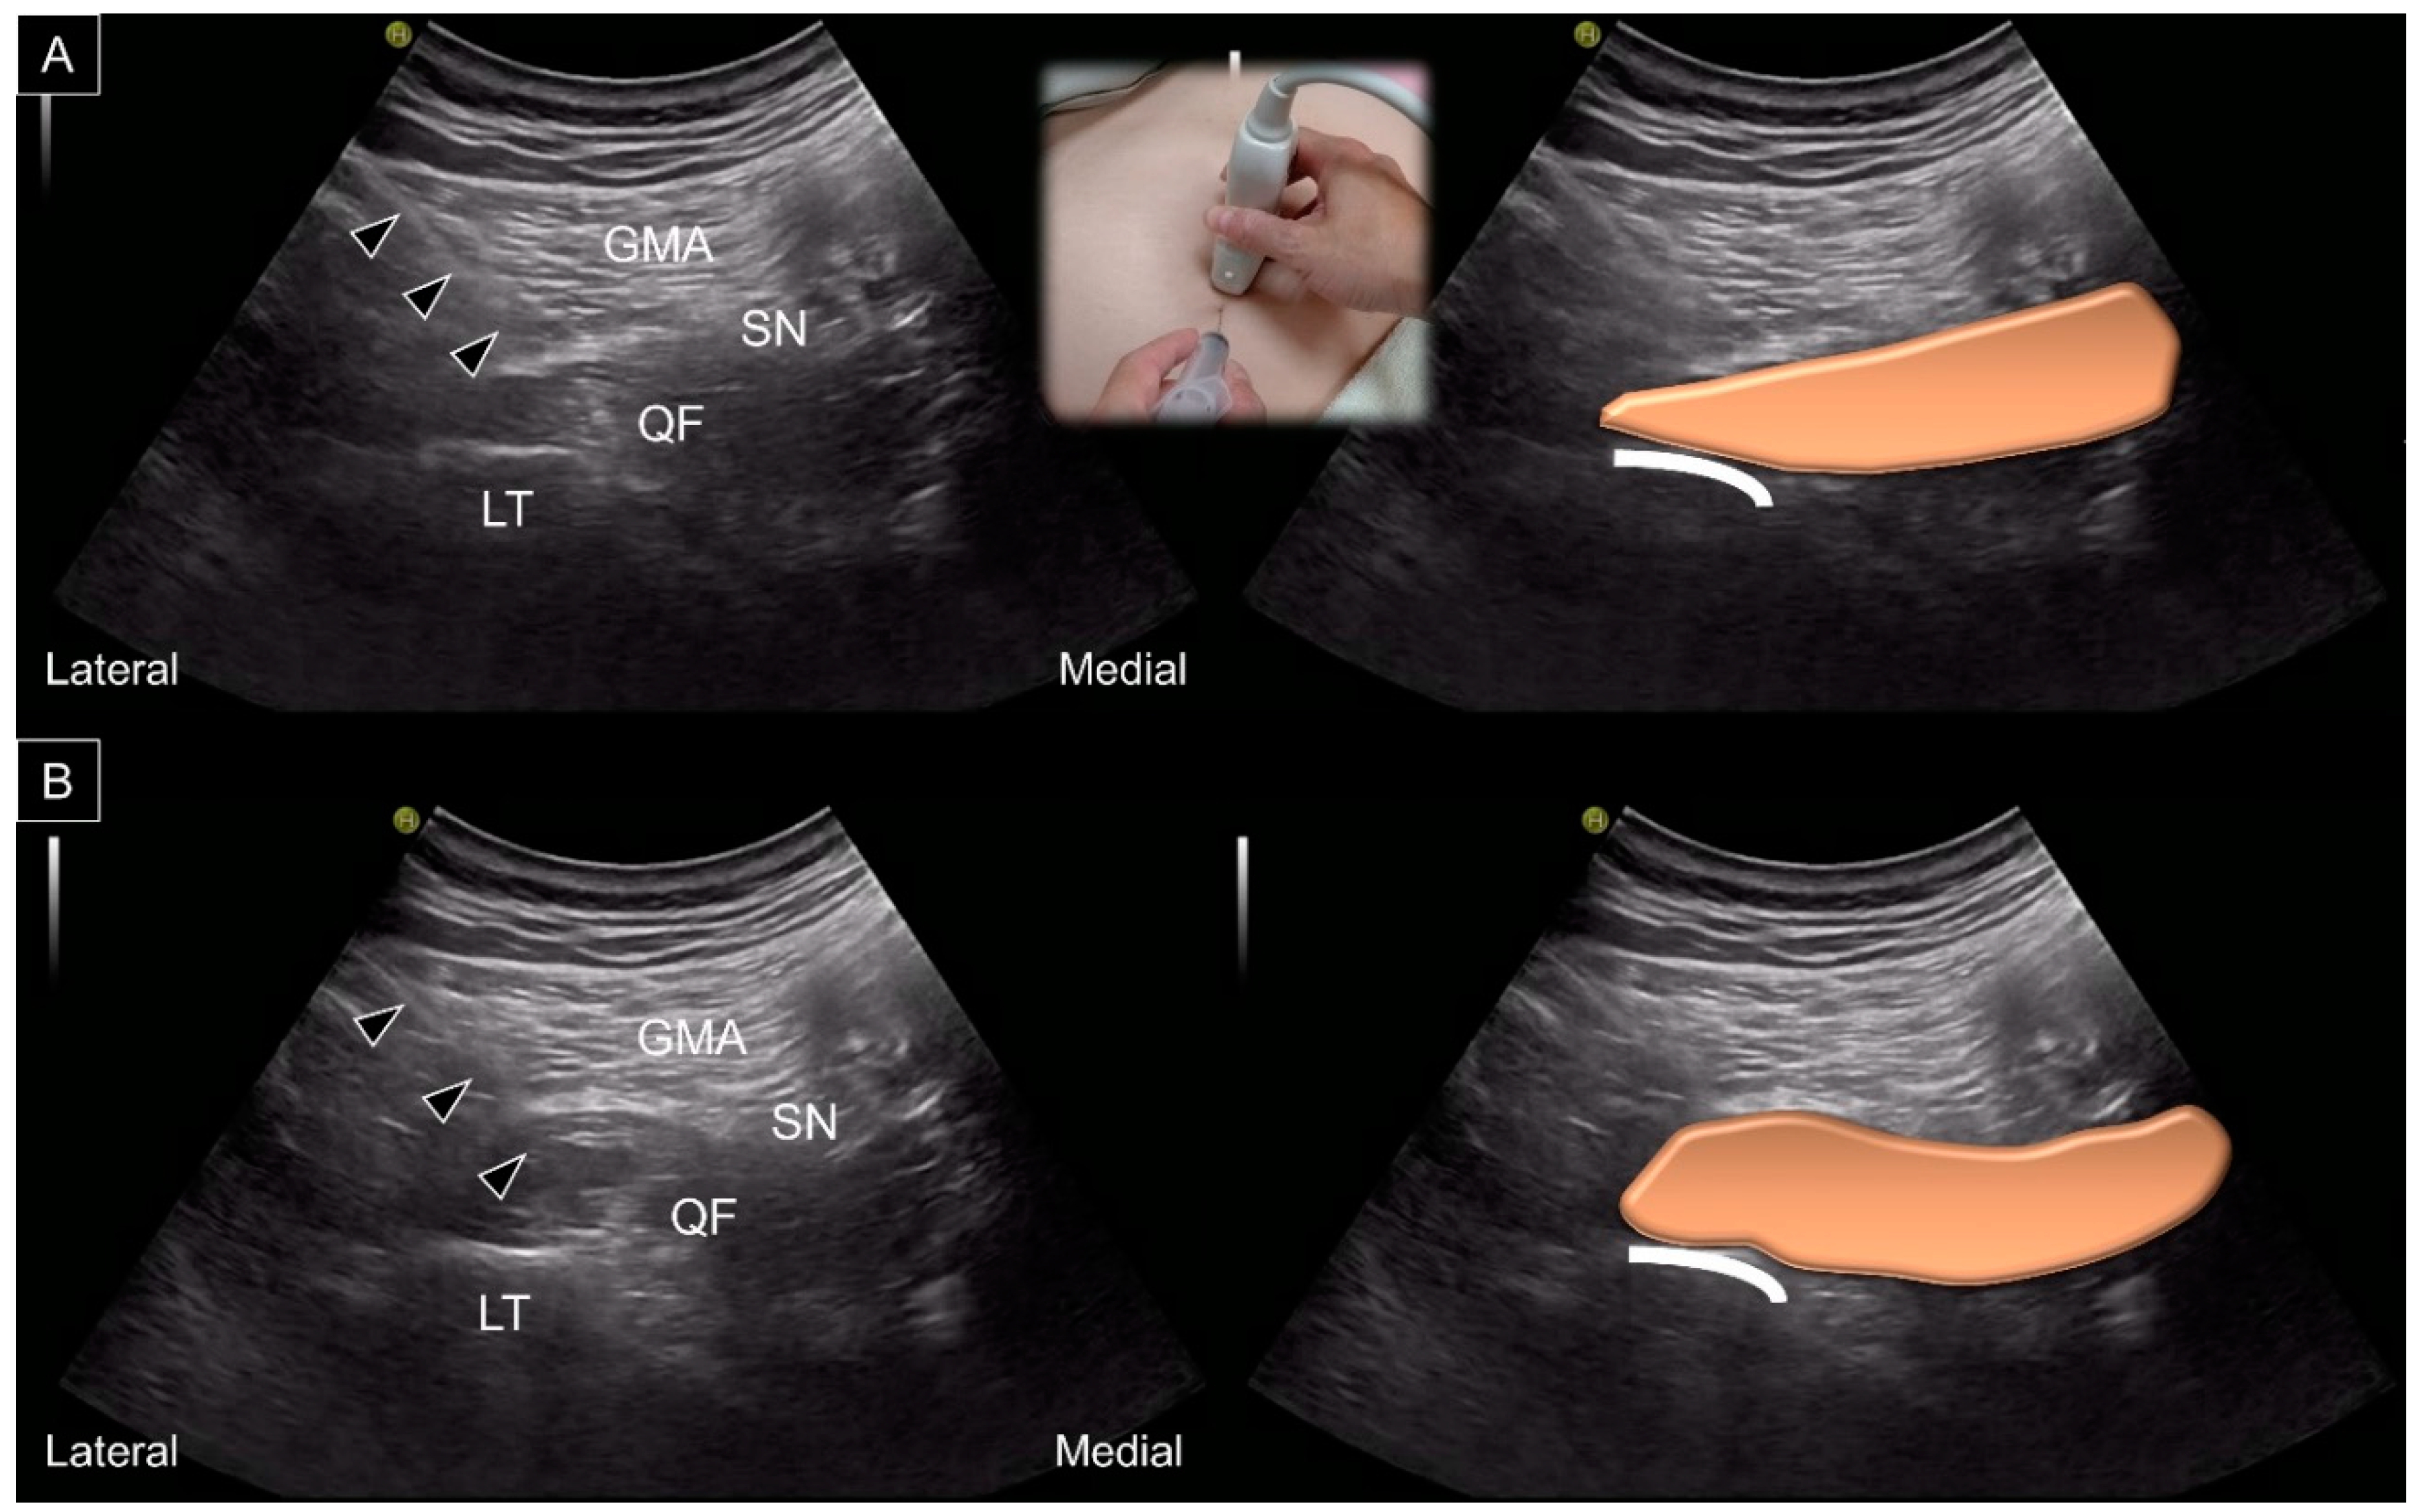

9. US-Guided Intervention